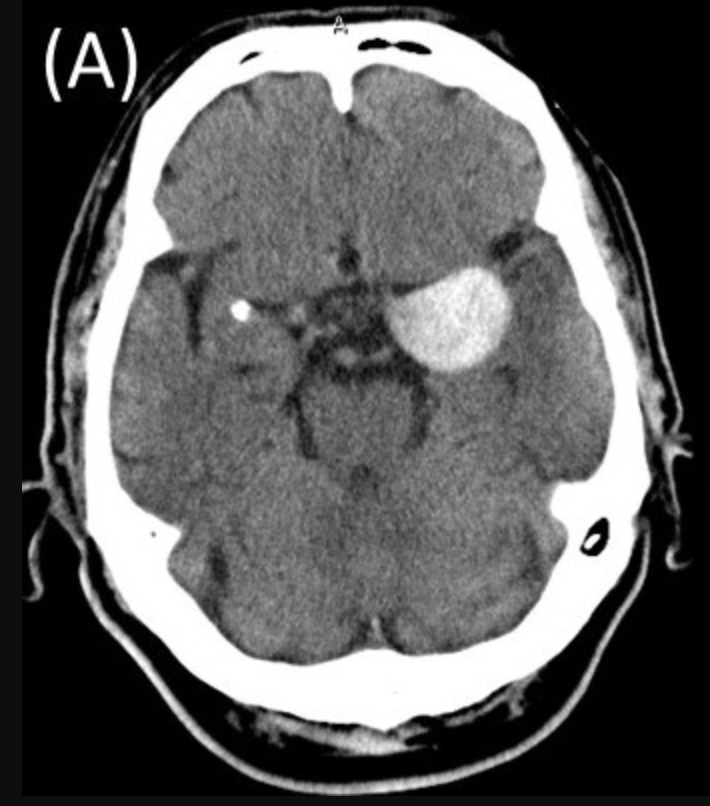

Como é feito o diagnóstico do aneurisma cerebral?

O aneurisma cerebral não é diagnosticado apenas pela consulta médica ou pelo exame físico e neurológico.

Ele é identificado por exames de imagem, que permitem ver os vasos do cérebro.

Na maioria das vezes, o aneurisma é descoberto por acaso, quando a pessoa faz um exame por outro motivo, como dor de cabeça, tontura ou investigação de esquecimento.

Os exames mais usados são:

- Angiotomografia arterial de vasos do crânio (Angio-TC)

É uma tomografia com contraste que mostra os vasos do cérebro.

É um exame rápido e bastante utilizado para investigar aneurismas.

- Angiorressonância arterial de crânio (Angio-RM)

É feita com ressonância magnética e também permite ver os vasos cerebrais.

Não usa radiação e, em muitos casos, pode ser feita sem contraste.

- 3. Angiografia Cerebral (ou arteriografia)

Em situações específicas, pode ser indicado um exame mais detalhado, chamado angiografia cerebral.

Esse exame é mais invasivo e costuma ser reservado para casos em que é preciso avaliar melhor o aneurisma ou planejar um tratamento.

Depois que o aneurisma é identificado, o médico avalia os exames para decidir se o aneurisma pode apenas ser acompanhado com consultas e exames regulares ou se precisa de algum tipo de tratamento.

Ter um diagnóstico claro traz mais segurança.

Quando o aneurisma é conhecido e acompanhado, é possível reduzir riscos e tomar decisões com calma e planejamento.